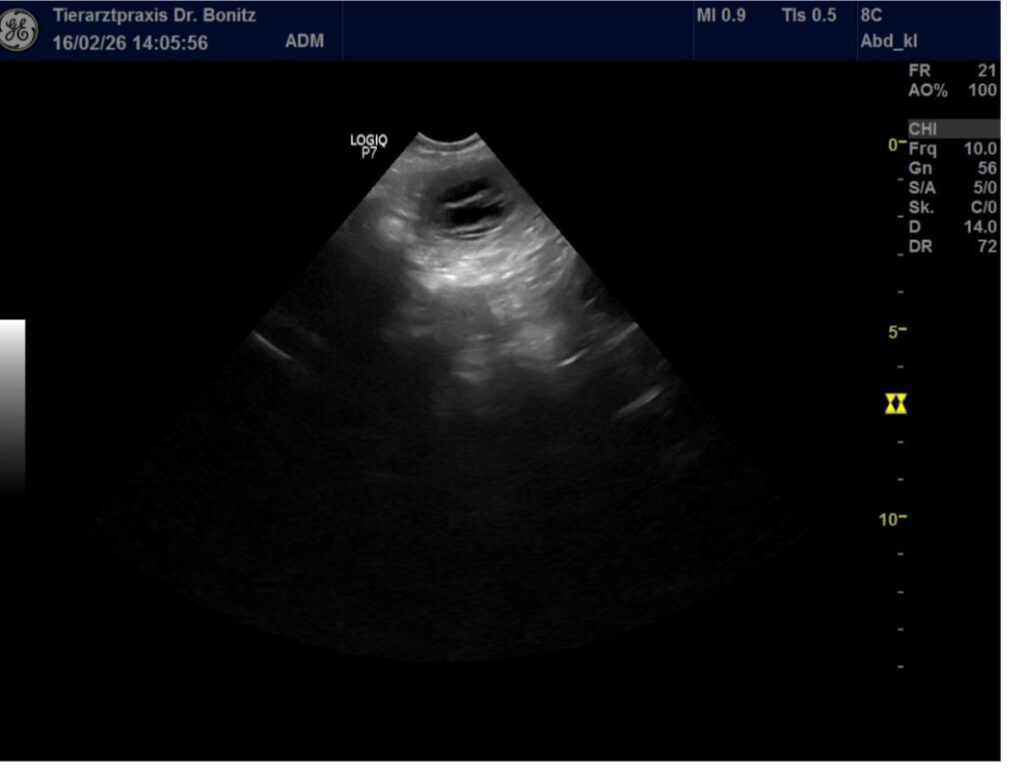

Wir waren am 17.02.2026 beim Trächtigkeitsultraschall und es konnten mindestens 4-5 Welpen gezählt werden. Die Entwicklung ist dem Trächtigkeitszeitpunkt entsprechend. Sheena lässt sich bisher noch immer nichts anmerken, was aber auch hier normal ist.